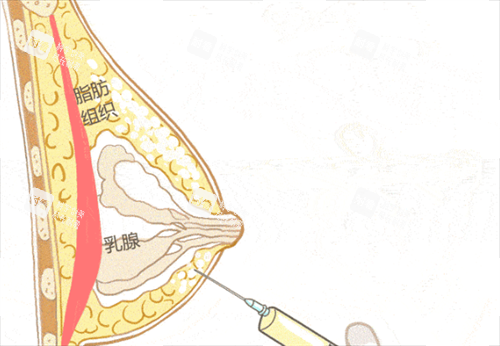

很多人以为奥美定取出就是“挖出来就行”,其实远远没那么简单。奥美定是一种水凝胶类物质,注射后会随着时间慢慢游走、分散,甚至包裹在组织里。如果用传统方式粗暴刮除,不仅容易残留,还可能伤到血管神经,反而加重术后反应。

现在正规医院普遍采用的是“全息六维层离清奥术”,配合3D内窥镜技术,就像给身体装了个高清导航仪——医生能清晰看到每一处奥美定的分布位置,逐层分离、温和稀释,避开重要组织,实现“干净又可靠”的取出。这种技术特别适合那些注射时间久、范围广的朋友,比如二十年前打过臀部或胸部的术例,也能被系统性清理干净。